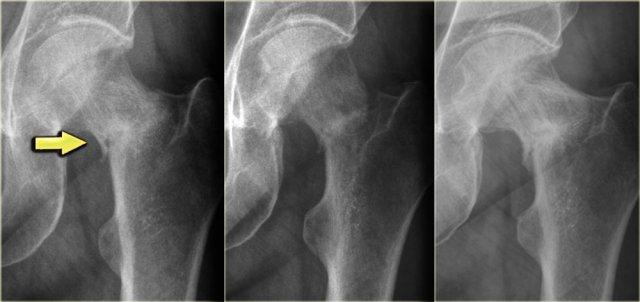

Đây là hình ảnh của một bệnh nhân có khối xơ cứng cạnh vỏ xương ở đầu trên xương cánh tay (trái).

Trường hợp này được xác định là vôi hóa phản ứng thứ phát sau chấn thương.

Lưu ý sự tương đồng với khối u cạnh vỏ xương ở một bệnh nhân khác (bên phải), được chẩn đoán xác định bằng sinh thiết là u xương cạnh màng xương (parosteal osteosarcoma).

Điều này cho thấy rằng việc phân biệt khối u với một quá trình phản ứng đôi khi có thể rất khó khăn trong một số trường hợp.

Khi một quá trình phản ứng có khả năng xảy ra hơn dựa trên tiền sử và đặc điểm hình ảnh, đôi khi vẫn cần theo dõi thêm.